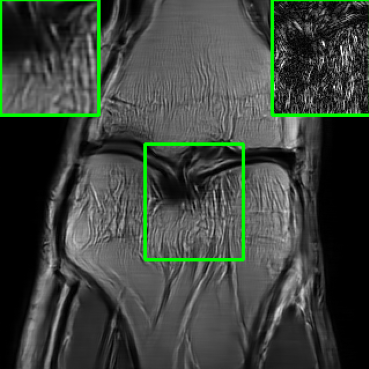

5.4 Visualizations

We now present visual samples from both the knee and brain datasets. Specifically, Figure 5 presents visual comparison of image reconstructions and their associated reconstruction errors within a closely examined region. Each image in the figure includes two inset panels in the top-left and top-right corners. The top-left inset panel, enclosed within a green bounding box, serves as a reference for the region of interest in the image. In contrast, the top-right inset panel depicts an error map in relation to the ground truth. Notably, our method stands out in its ability to capture the original image’s features, surpassing the performance of alternative methods (as also evident from the reported PSNR values). This visual comparison underscores the superior quality and accuracy of our approach in the robustification of the MRI image reconstruction task.